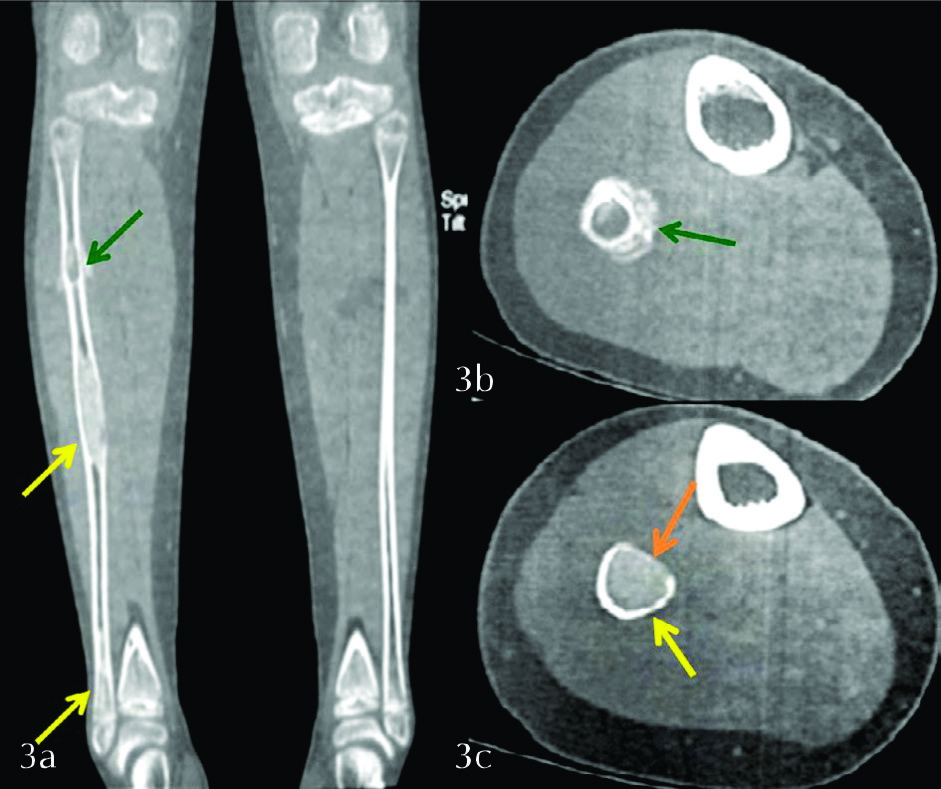

Figura 3

TC de MMII con filtro duro. a) Corte seleccionado en el plano coronal, b) Corte seleccionado en el plano axial de la lesión superior, c) Corte seleccionado en el plano axial de la lesión del tercio medio. Se observa con mayor precisión la reacción perióstica de la lesión proximal (flechas verdes), la cual es ininterrumpida, de tipo sólido. El resto de las lesiones no presentan reacción perióstica de ningún tipo. Véase la matriz en “vidrio deslustrado” presente en las tres lesiones (flechas amarillas). Se identifica expansión y adelgazamiento de la cortical (flecha naranja).